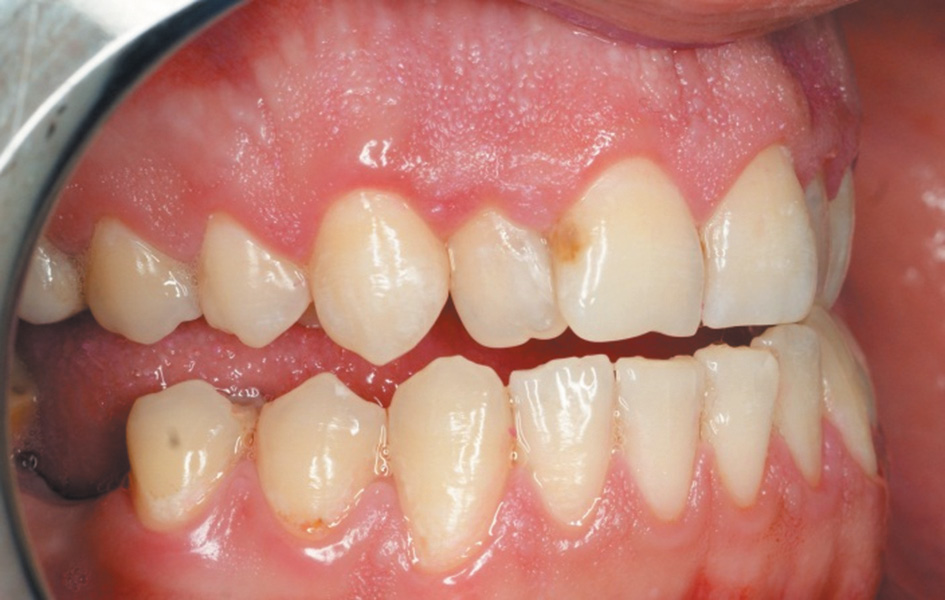

Пациентам второй группы (8 человек) проводили профессиональную гигиену полости рта с использованием современного ультразвукового аппарата AIRFLOW Prophylaxis Master (EMS) и обработку поверхностей зубов по технологии Air Flow с использованием мелкодисперсного порошка «Plus». В отличие от стандартного протокола проведения профессиональной гигиены, данный протокол — GBT (Guided Biofilm Therapy) — предусматривает изменение порядка проведения процедур. Перед началом процедуры мы предварительно визуализируем мягкий зубной налет с помощью двухфазного красителя, используя специальные губки (рис. 1).

Рис. 1. Индикация двухфазным красителем назубных отложений у пациента с гемофилией

Fig. 1. Two-phase staining of teeth deposits in patients with haemophilia